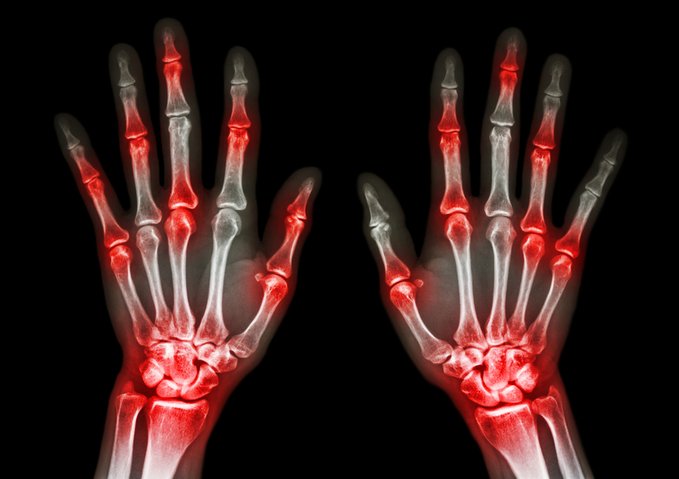

Avances en el tratamiento de la artritis psoriásica en adultos

Esta revisión describe las herramientas de evaluación y las medidas de resultado utilizadas en la evaluación de los pacientes con artritis psoriásica. Resume el enfoque de la terapia, incluidas las intervenciones no medicinales como la educación, los cambios en el estilo de vida, la fisioterapia y la terapia ocupacional. Se discute la evidencia sobre los tratamientos farmacológicos, incluidos los fármacos utilizados para el alivio sintomático, como los antiinflamatorios no esteroideos, y los utilizados para controlar el proceso de la enfermedad. BMJ 21 de noviembre de 2024